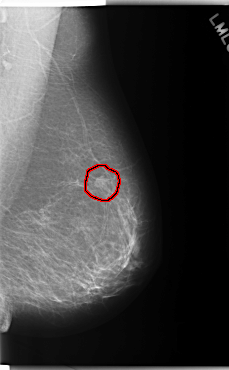

C_0187_1.LEFT_MLO

LEFT_MLO LINES 5920 PIXELS_PER_LINE 3664 BITS_PER_PIXEL 12 RESOLUTION 50 OVERLAY

FILE: C_0187_1.LEFT_MLO.OVERLAY

TOTAL_ABNORMALITIES 1

ABNORMALITY 1

LESION_TYPE MASS SHAPE OVAL MARGINS SPICULATED

ASSESSMENT 5

SUBTLETY 5

PATHOLOGY MALIGNANT

TOTAL_OUTLINES 1

BOUNDARY